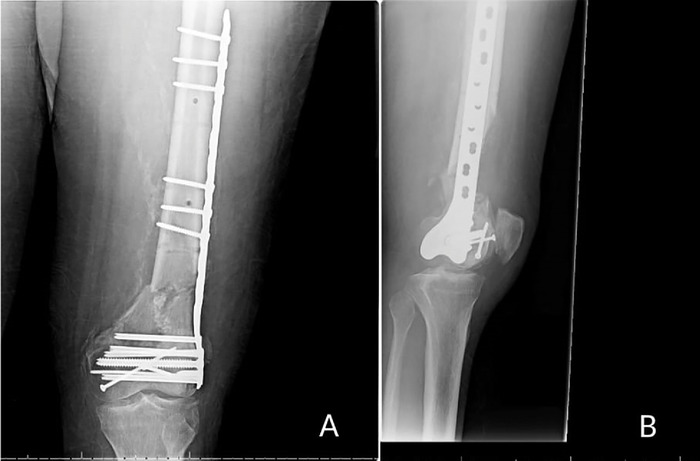

Case report: A 54-year-old male was involved in a high-speed motor vehicle accident that resulted in a left distal femur fracture. The patient underwent multiple reconstructive procedures that were complicated by hardware failure and recurrent nonunion. Prior to the sixth reconstruction, a superficial femoral artery occlusion was discovered and addressed with endarterectomy. The sixth and final procedure resulted in osseous union and stable fixation of the femur fracture.

Conclusion: A missed superficial femoral artery occlusion likely contributed to the delay in achieving osseous union of a traumatic comminuted distal femur fracture.